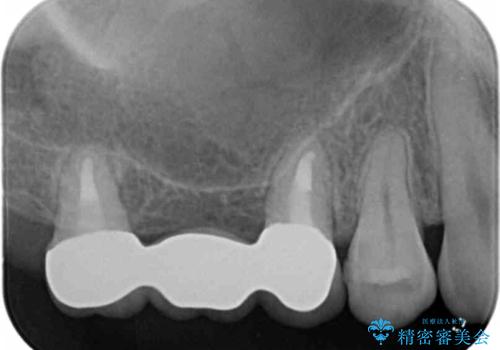

使っていない親知らず(右上8)を右上7抜歯窩に移植し、支台歯としてブリッジによる補綴治療を行いました。

インプラントや入れ歯を使わずに奥歯でしっかり咬むことができるようになり、また見た目も自然だと大変喜んで頂けました。

クラウンの種類:メタルボンドクラウン エコノミー フルベイク